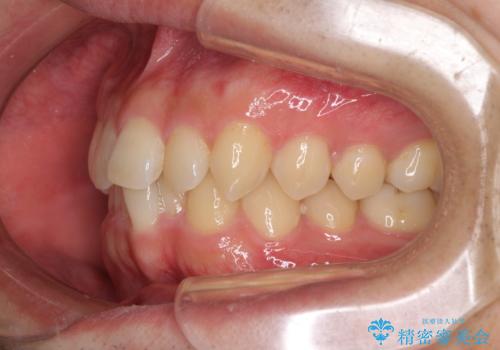

- 上下前歯のデコボコと深い咬み合わせを気にして来院された患者様です。

インビザラインによる上下歯列の拡大と、IPR(歯と歯の間を削る)にるスペースの獲得により、前歯のデコボコとディープバイトを改善することとしました。

もう少し下の前歯を整えたかったのですが、患者様の治療を早く終了させたいという希望により、細かい叢生を残しての終了となりました。